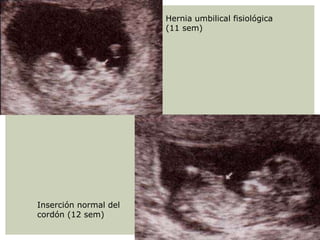

Parte del intestino protruye en la

base del cordón umbilical (Hernia

umbilical fisiológica)

Hernia umbilical fisiológica

(11 sem)

Inserción normal del

cordón (12 sem)